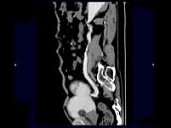

男,72岁,排尿困难1年余,无手术病史,CT扫描如图所示,下列说法正确的是?(?)

• A.一侧肾脏缺如

• B.膀胱的后上方可见一囊性肿物,该囊性肿物与膀胱相通

• C.考虑为先天性孤立肾

• D.该囊性肿物考虑为膀胱憩室

• E.该囊性肿物考虑为输尿管囊肿